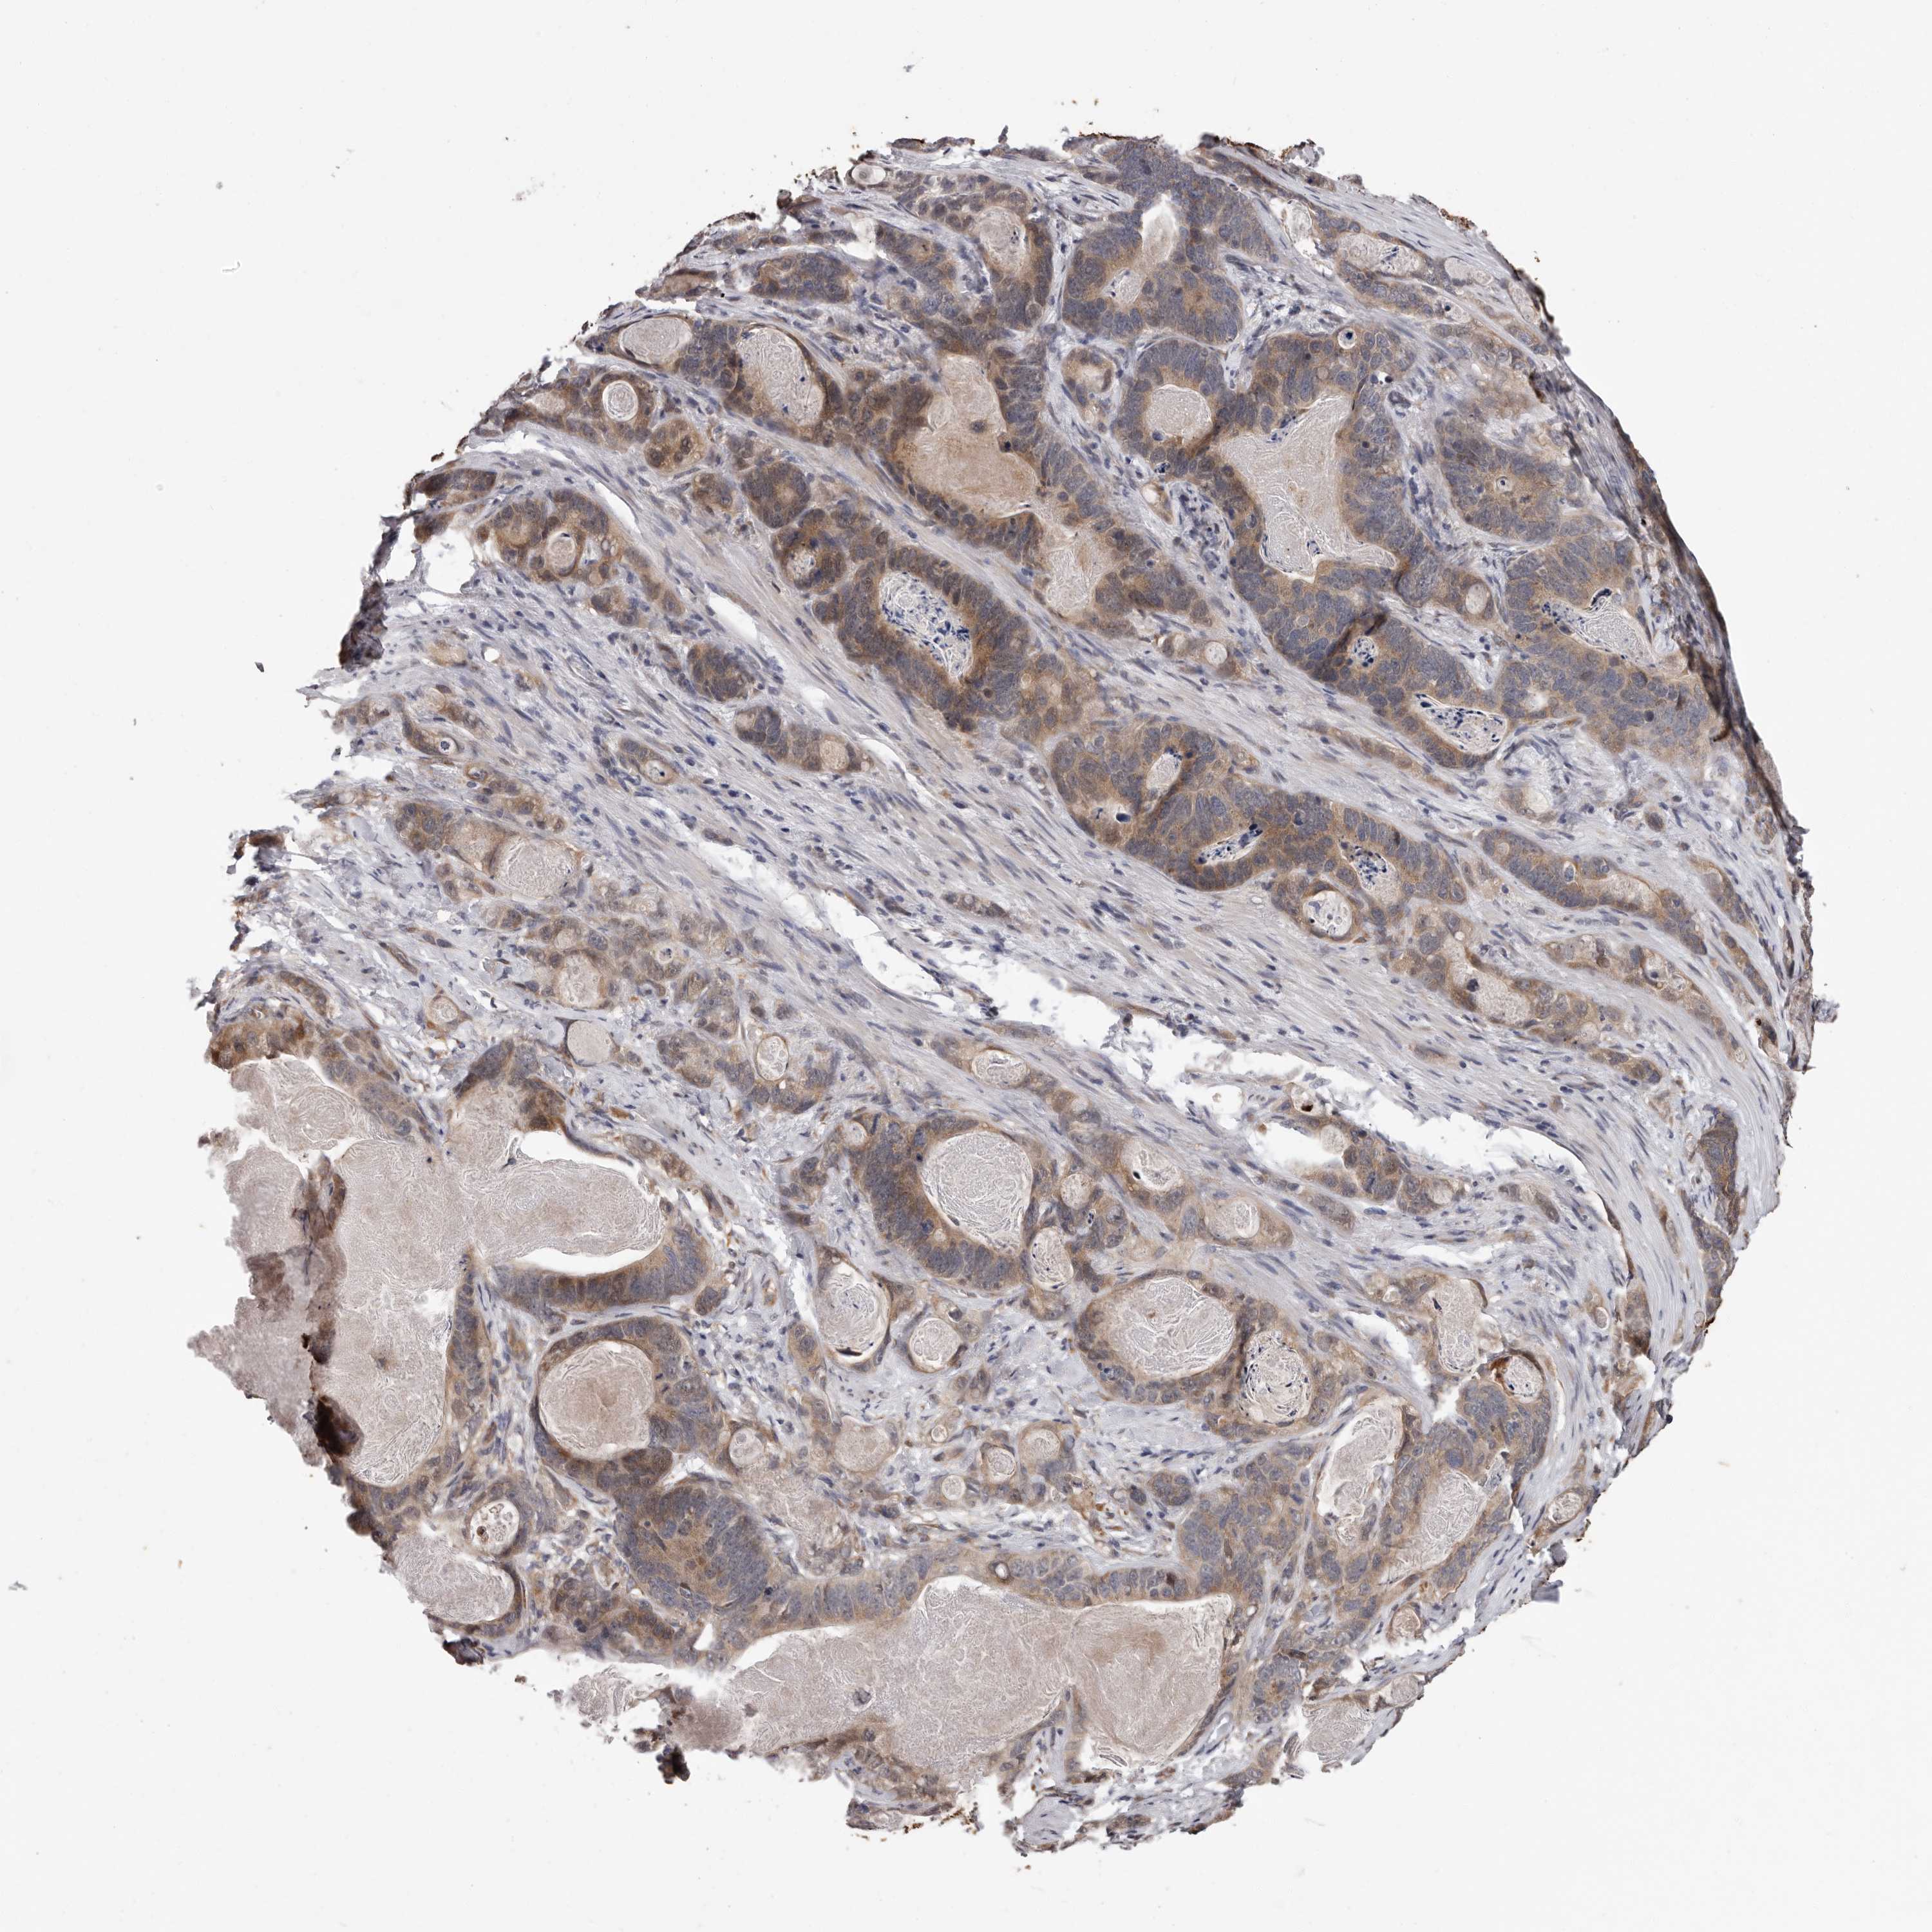

STOMACH CANCER - Protein expressioni

A mouse-over function shows sample information and annotation data. Click on an image to view it in a full screen mode. Samples can be filtered based on level of antibody staining by selecting one or several of the following categories: high, medium, low and not detected. The assay and annotation is described here.

Note that samples used for immunohistochemistry by the Human Protein Atlas do not correspond to samples in the TCGA dataset.

Antibody stainingi

Antibody staining in the annotated cell types in the current human tissue is reported as not detected, low, medium, or high, based on conventional immunohistochemistry profiling in selected tissues. This score is based on the combination of the staining intensity and fraction of stained cells.

Each image is clickable and will lead to virtual microscopy that enables deeper exploration of all samples and also displays staining intensity scores, fraction scores and subcellular localization as well as patient and tissue information for each sample.

Antibody HPA028377

Antibody HPA028438

Staining

High

Medium

Low

Not detected

Intensity

Strong

Moderate

Weak

Negative

Quantity

>75%

75%-25%

<25%

None

Location

Nuclear

Cytoplasmic/membranous

Cytoplasmic/membranous,nuclear

Adenocarcinoma, NOS